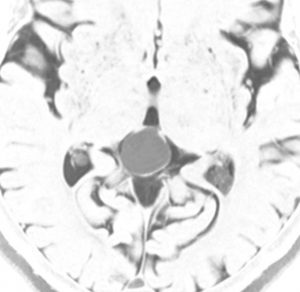

若い女性にできた,症状の全くない松果体のう胞です。右側は拡大図で,8 mmくらいの大きさでしょうか。もちろん何もする必要はありません。たくさん発見されるものです。